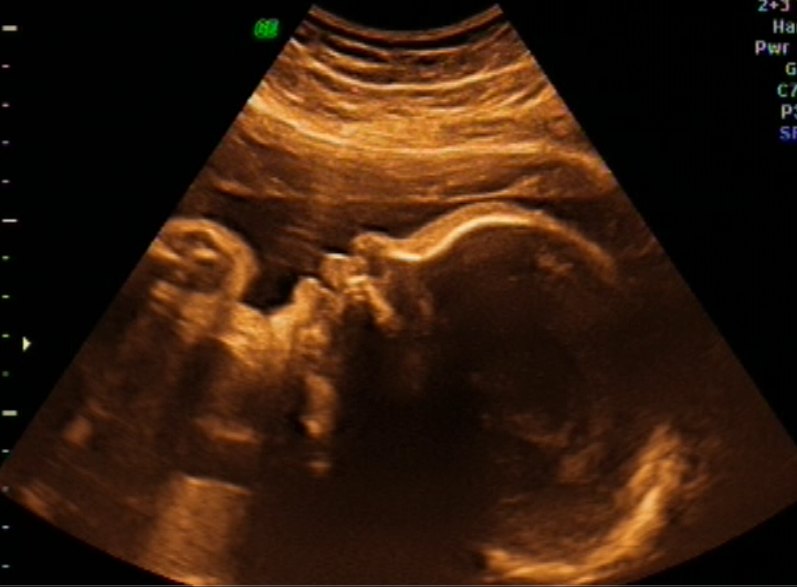

Vi har været til 3D-scanning i dag, og lillepigen har det bare helt fantastisk inde i maven

Hun ligger en lille smule under gennemsnittet, men ikke ret meget, så det er jo helt perfekt - 1494 gram baby-prinsesse

Og så fik vi og vide, at hun har masser af hår og at det er lige knap 2 cm. langt - så kan slet ikke vente med at få hende i mine arme

3D-billederne blev ikke ret godt, da hun lå med både arme og ben oppe foran hovedet, men vi fik da et lille kig ind til vores kommende datter og resten må vente til hun kommer til verden